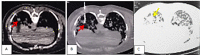

More than 40 different species of the parasitic flatworm Paragonimus have been identified worldwide, including in Vietnam, but only 10 species are known to cause disease in humans, particularly Paragonimus westermani. Paragonimus are transmitted through the ingestion of raw foods, especially freshwater shrimp, and crab. Paragonimiasis causes pneumonia, which can present as acute or chronic, with symptoms including prolonged cough, chest pain, shortness of breath, and hemoptysis. Hematologic changes include eosinophilia and the presence of specific antibodies for Paragonimus in the blood. Diagnosis is confirmed when Paragonimus specimens or eggs are found in the sputum or pleural fluid. The specificity of imaging is not high, but imaging can be used to guide the diagnosis. After the failure of microbiological diagnostic methods, lung biopsy can be used to confirm a diagnosis of paragonimiasis. We present a paragonimiasis case associated with unique features, including epidemiologic factors, atypical clinical signs, no increases in blood eosinophils, and negative microbiological tests. Although the patient was suspected of tuberculosis or lung cancer, imaging studies were consistent with the presence of lung flukes. Three transthoracic lung biopsies were performed, and pathology revealed a cystic structure containing Paragonimus on the third biopsy.